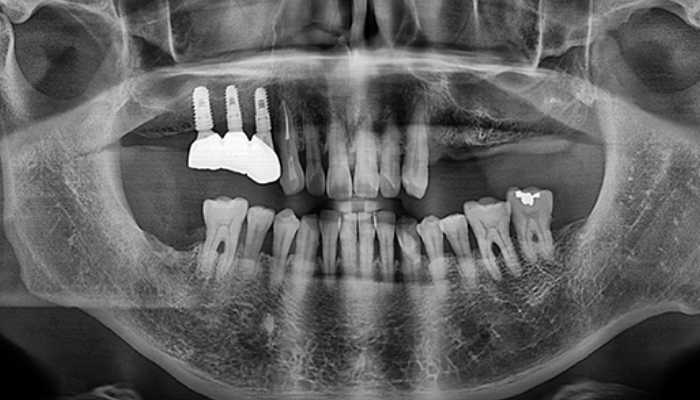

뼈이식 / 임플란트 식립공간 확보

잇몸을 절개하고 난 후 뼈를 넣고 상악동을 들어 올릴만한 작은 통로를 만들어 뼈이식할 공간과 임플란트 식립할 공간을 확보합니다.

잇몸 뼈이식 시술 진행

들어올린 빈 공간에 뼈를 이식하는데 이때 사용되는 뼈이식 재료로는 자가치아뼈, 자가골, 인공뼈, 합성골 등이 있습니다.

임플란트 매식체 식립

잔존하고 있는 잇몸뼈의 양에 따라 뼈이식과 동시에 임플란트 식립하기도 하고 6-9개월 후 식립하기도 합니다.